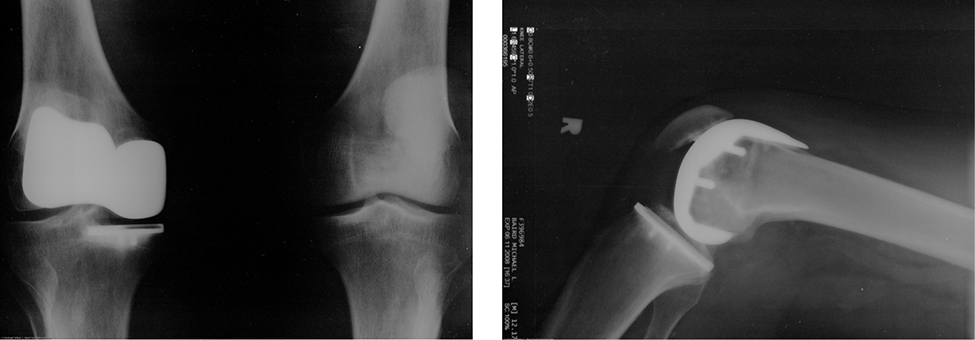

Many people have experienced the slipperiness of walking on ice. However, many parts of the body, especially the joints, have much smaller coefficients of friction—often three or four times less than ice. A joint is formed by the ends of two bones, which are connected by thick tissues. The knee joint is formed by the lower leg bone (the tibia) and the thighbone (the femur). The hip is a ball (at the end of the femur) and socket (part of the pelvis) joint. The ends of the bones in the joint are covered by cartilage, which provides a smooth, almost-glassy surface. The joints also produce a fluid (synovial fluid) that reduces friction and wear. A damaged or arthritic joint can be replaced by an artificial joint (Figure 6.12). These replacements can be made of metals (stainless steel or titanium) or plastic (polyethylene), also with very small coefficients of friction.